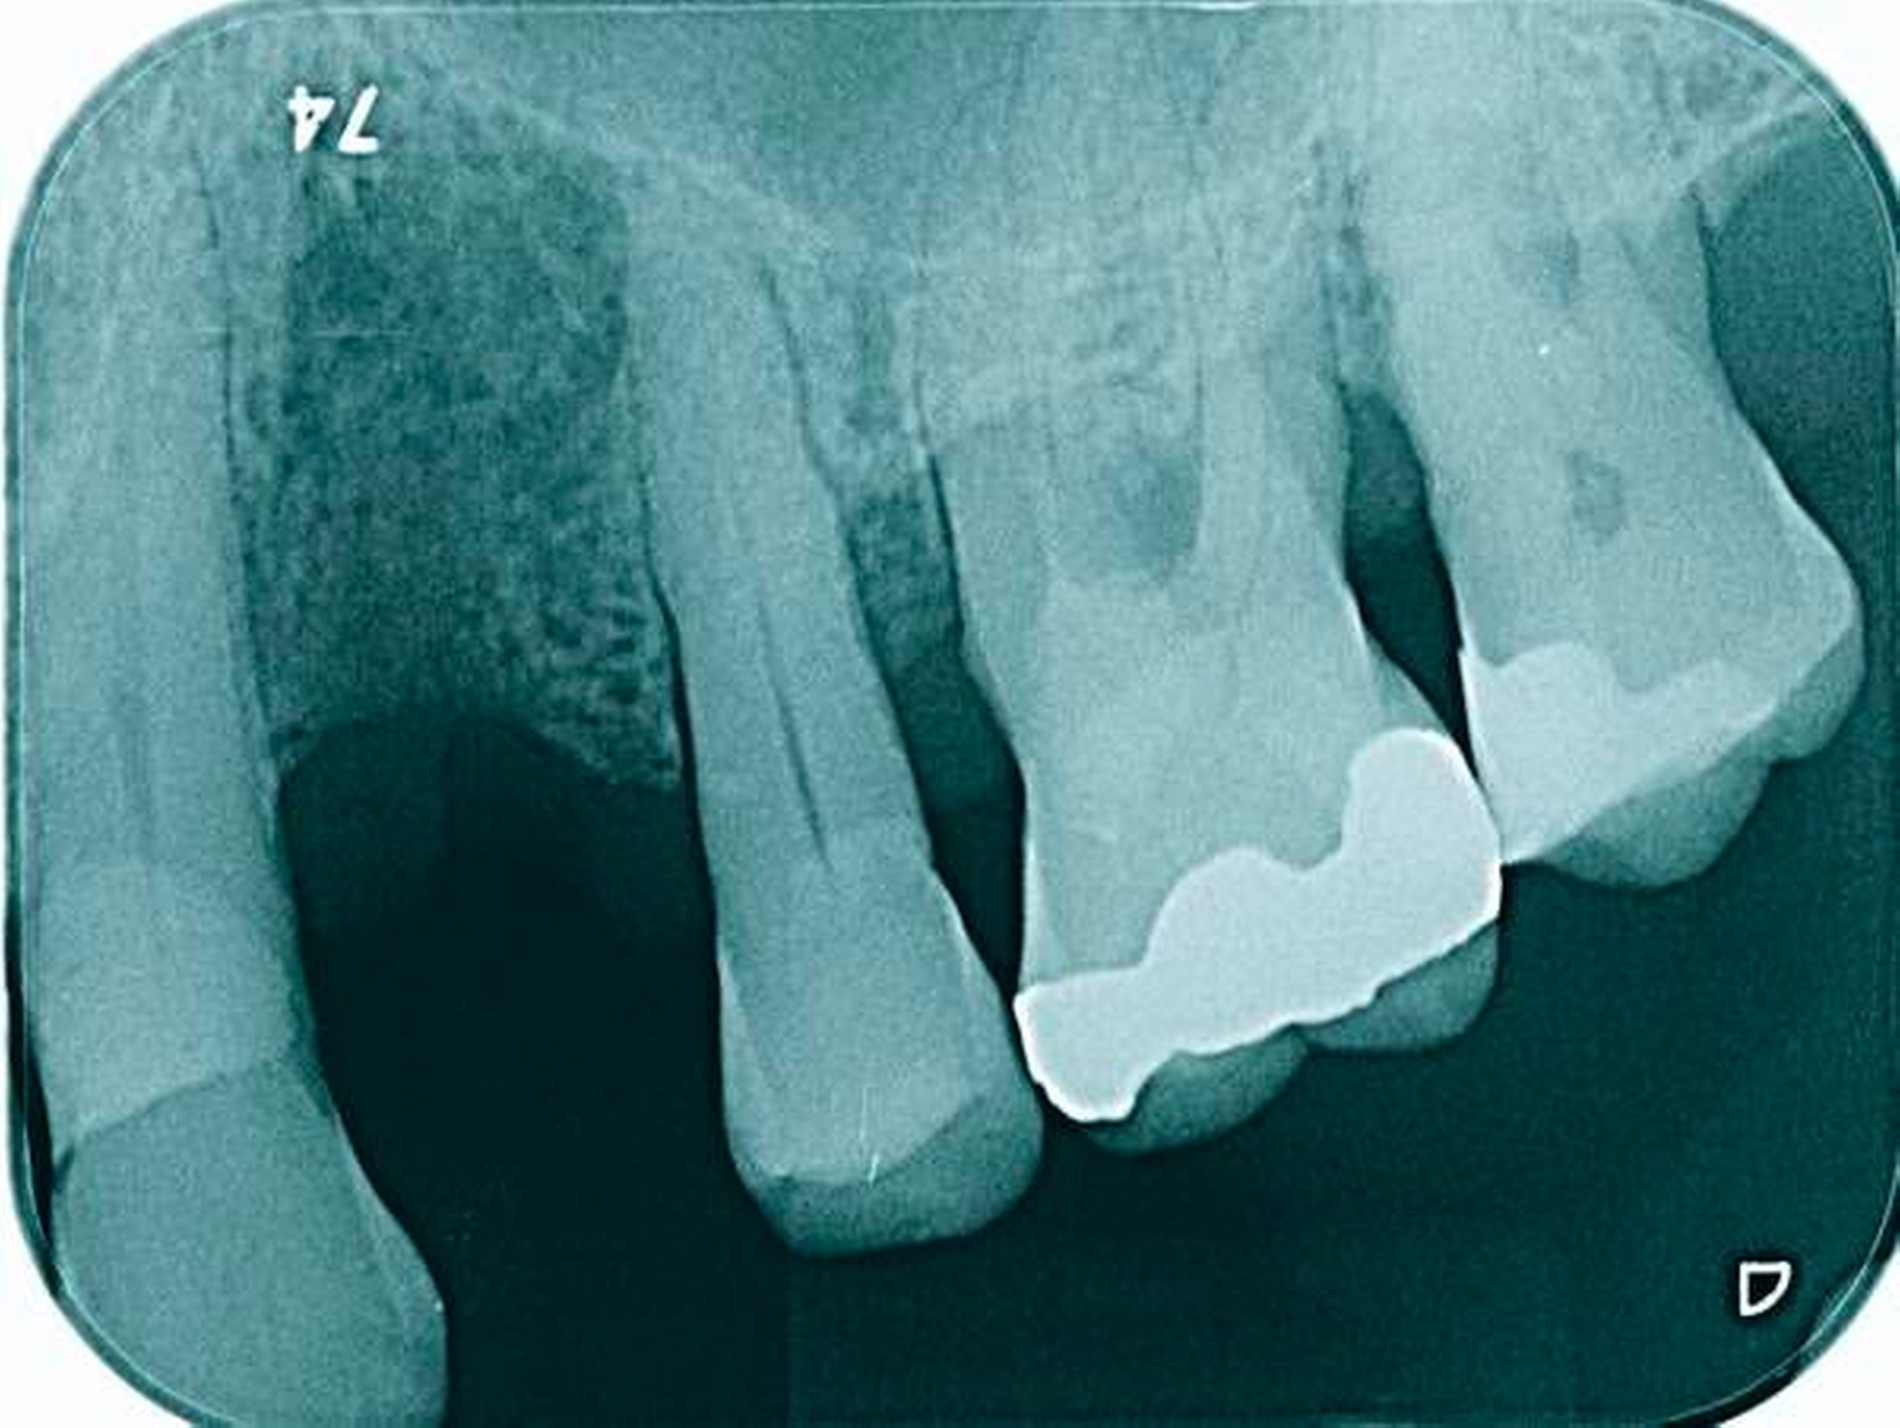

Abbildung 1a bis 1f: Direkte Überkronung im Frontzahnbereich (R1-Technik)

In den Abbildungen 1 bis 3 werden Optionen für frugale Interventionen auf restaurativem Sektor aufgeführt. Es handelt sich um direkte Vollüberkronungen im Frontzahnbereich (hier: hergestellt in R1-Technik / einphasig) (Abbildung 1), direkte Teilüberkronungen im Seitenzahnbereich (hier: hergestellt in R1-Technik / einphasig) (Abbildung 2), Reparatur-Restaurationen im Seitenzahnbereich (hier: hergestellt in R2-Technik / zweiphasig) (Abbildung 3). Technische Einzelheiten zur Vorgehensweise und den Ergebnissen sind an anderer Stelle beschrieben (Literatur siehe oben).

Am Beispiel von Abbildung 1 (stark zerstörte Zahnkrone eines Schneidezahns) kann das Prinzip der frugalen Intervention erläutert werden:

Für die in Abbildung 2 dargestellte Situation eines tief zerstörten Prämolaren gelten ähnliche Charakteristika. Es gibt in der restaurativen Zahnheilkunde viele Neuerungen, die das Behandlungsspektrum vergrößert haben. Dazu zählen unter anderem: